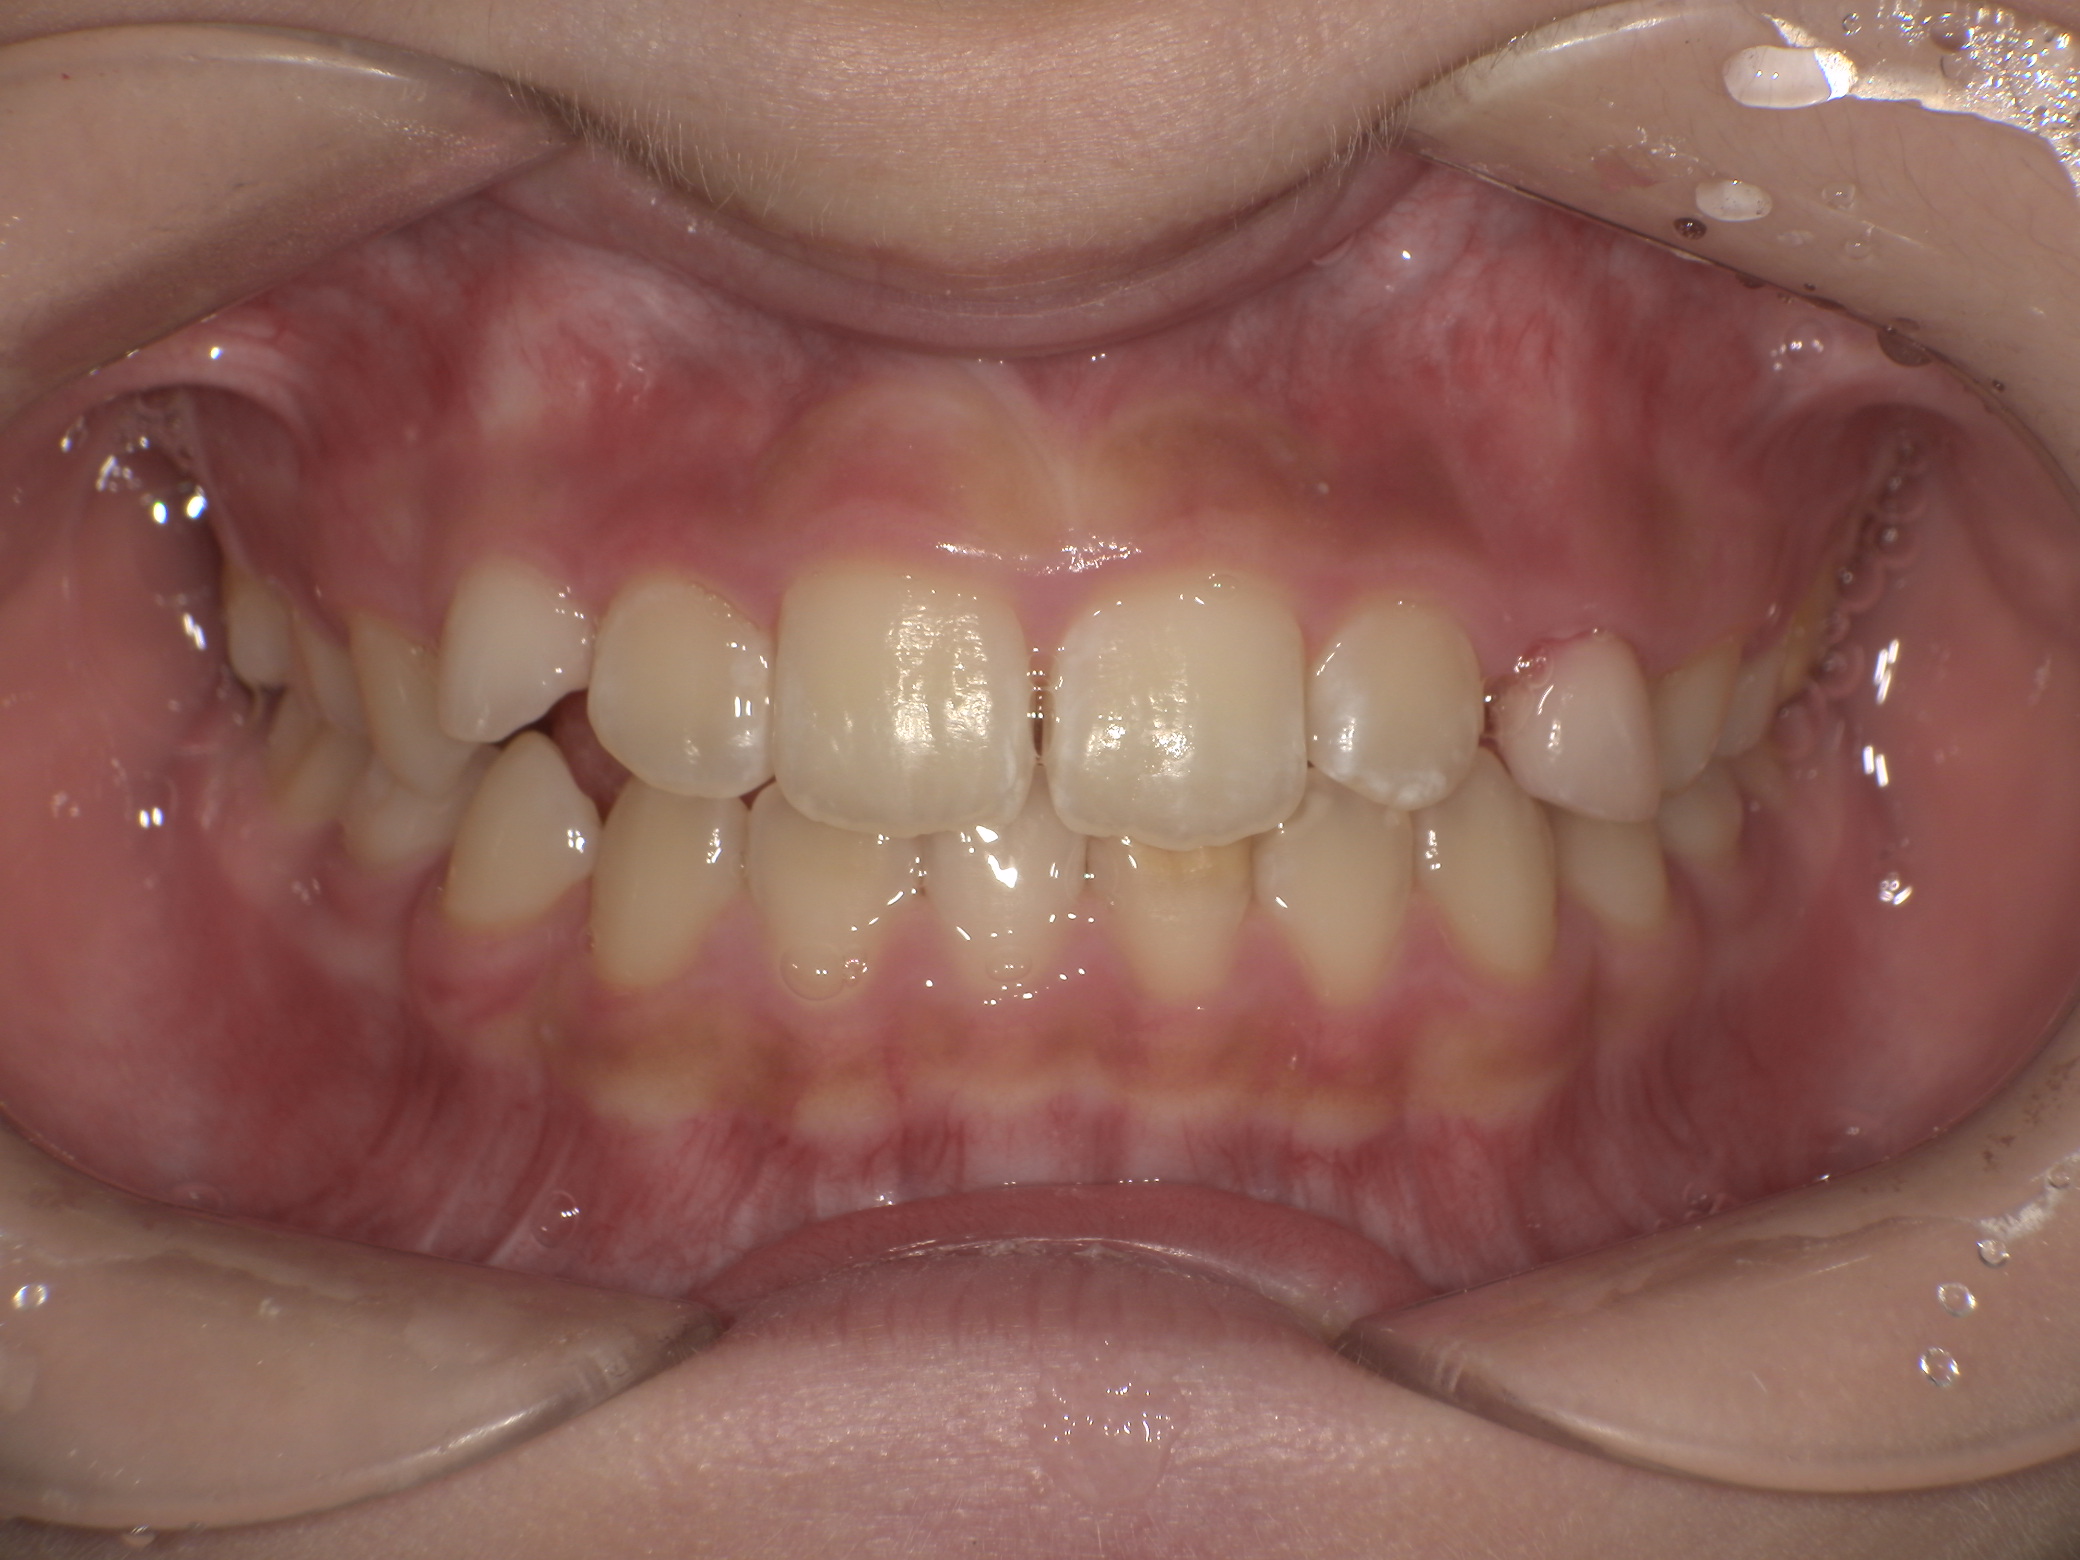

After

治療終了時(10歳1か月)